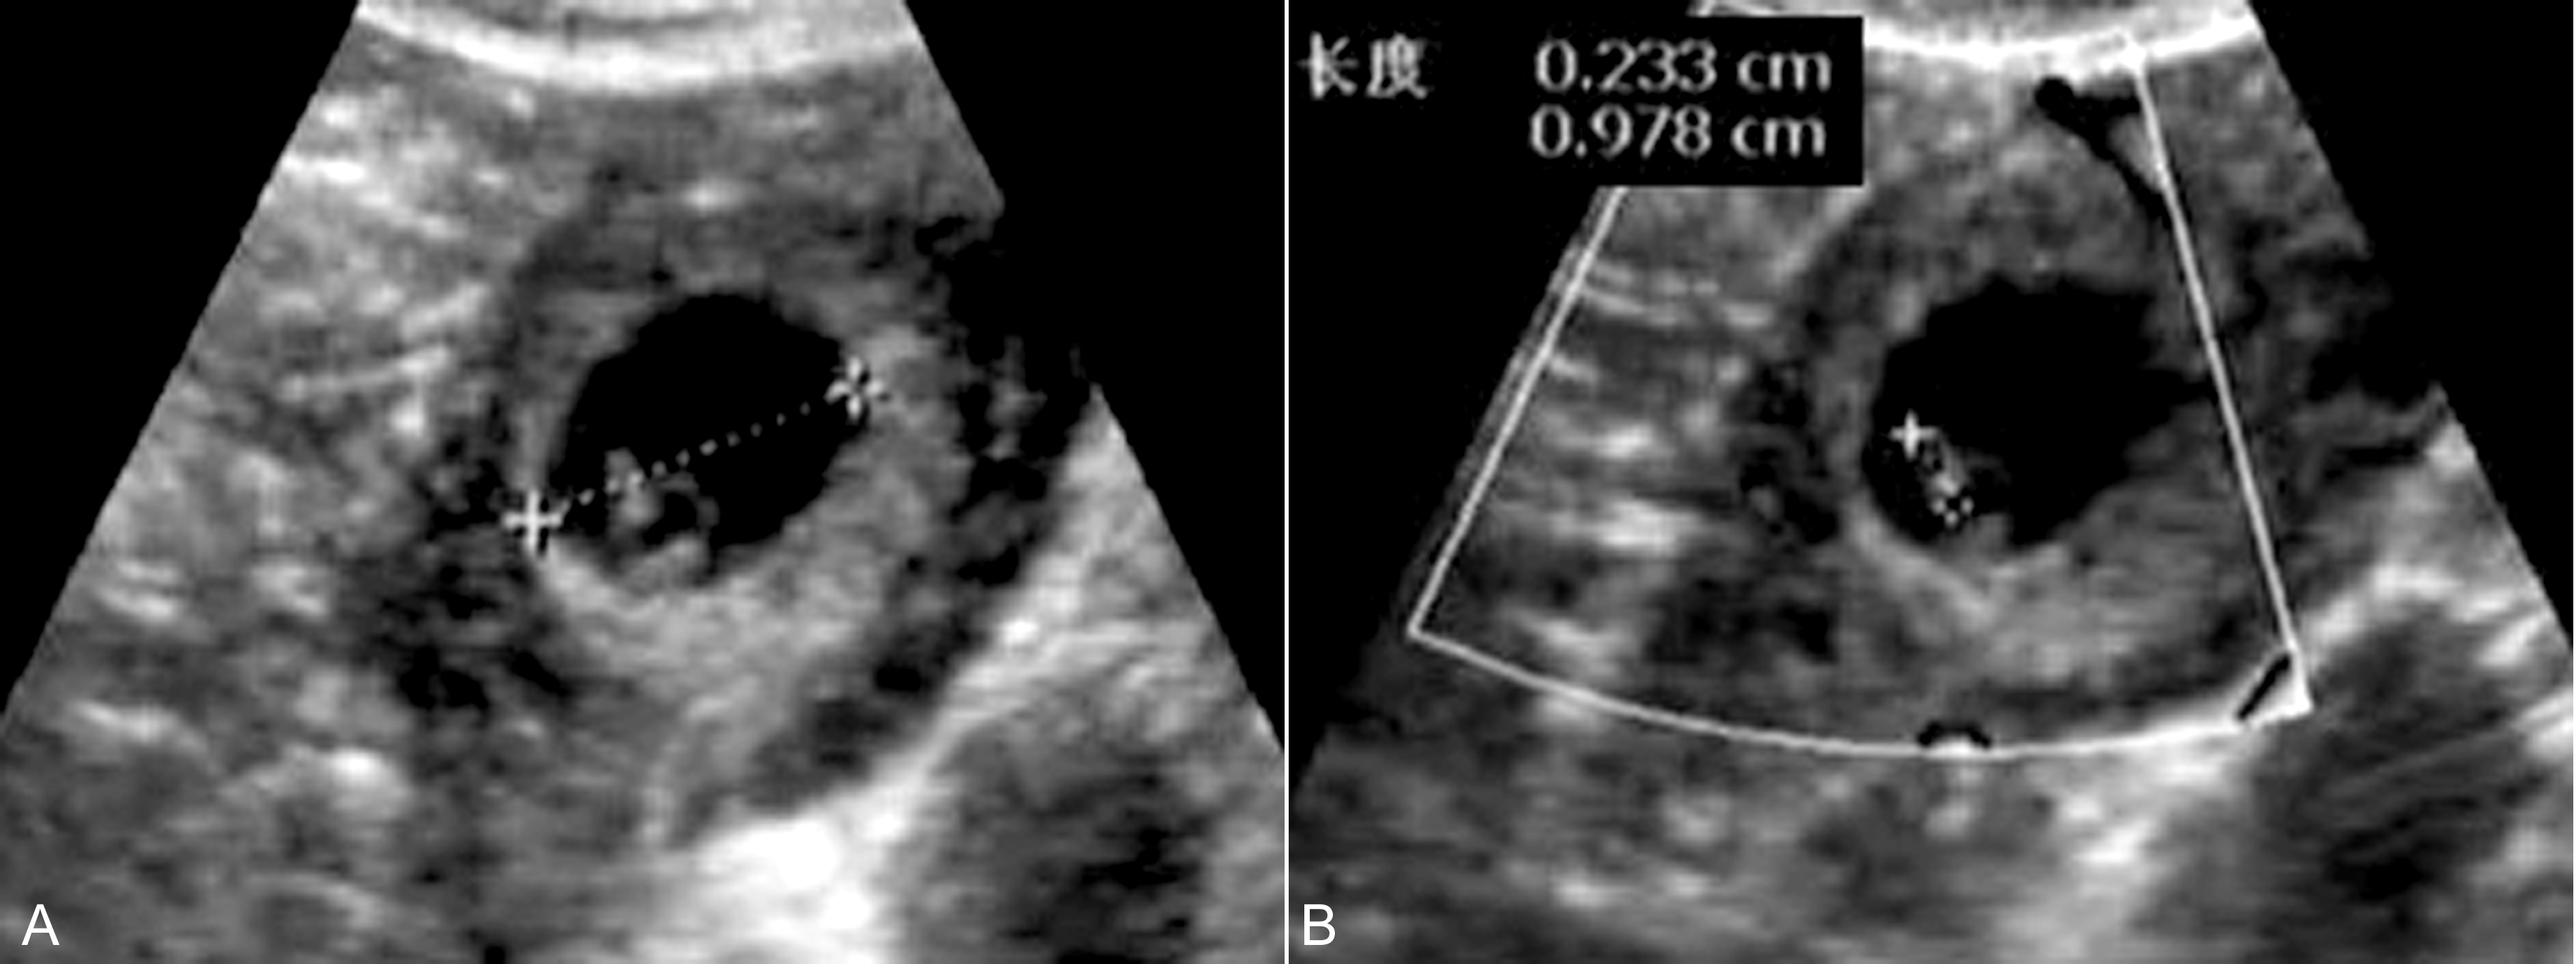

图2宫外孕并宫内积液:B:TVU宫腔内示梭形无回声;C:TVU示宫腔内椭圆形无回声

图4 输卵管妊娠:右侧附件区显示完整孕囊回声,胚胎2.3mm